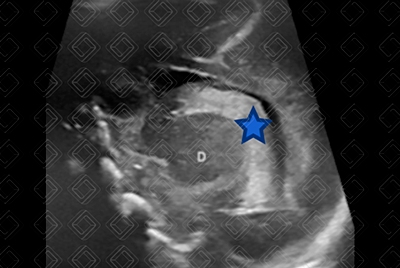

Descrição das figuras 3, 4 e 5: Ultrassonografia transfontanela; imagens coronais e parassagital direita. Área ecogênica visualizada no interior do corno frontal do ventrículo lateral direito (seta vermelha), estendendo-se no corte parassagital direito no interior do ventrículo lateral deste lado (estrela), deixando o plexo coroide (PC) deste lado mais “gordinho” e irregular em comparação ao esquerdo (seta amarela), compatível com hemorragia de matriz germinal grau II à direita. Nesse caso, não há dilatação do sistema ventricular.

• Grau II: H emorragia estendendo-se para o sistema ventricular, notadamente o plexo coroide, sem causar dilatação do sistema ventricular (figuras 3, 4 e 5);